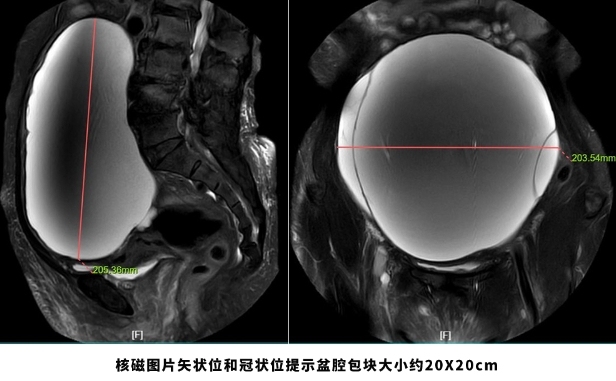

腾讯新闻网页版:69岁老妇挺着“大肚子”来医院,检查后竟“怀”了个巨大肿瘤!